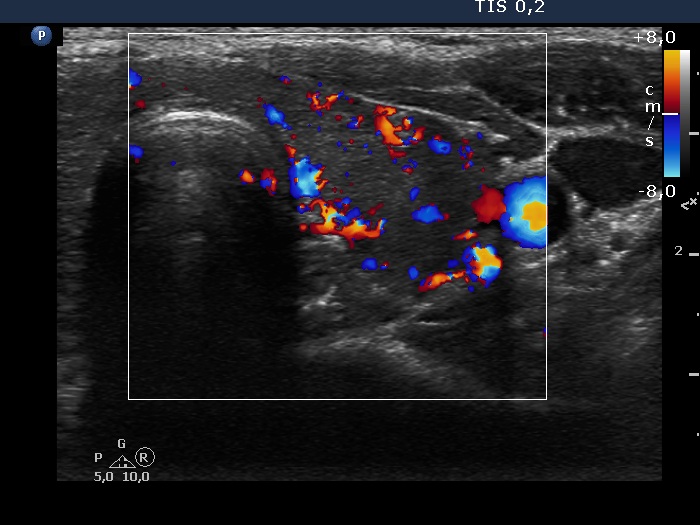

Lymphocytic thyroiditis - case 1580

Nine months after delivery (ultrasonographic picture 6)

Left lobe, transverse scan, color Doppler mode. The vascularity of this lobe has also increased.